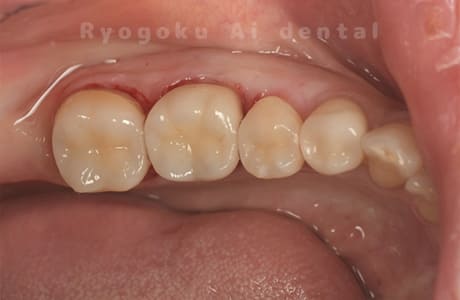

Case11

- 治療内容

- セラミッククラウン、セラミックインレー

-

- 治療費用

- 123,000円×2(セラミッククラン)、77,000円(セラミックインレー)

銀歯が取れて、ご来院された患者様です。奥歯2本をセラミッククラウン、手前の小臼歯をセラミックインレーで治療を行いました。